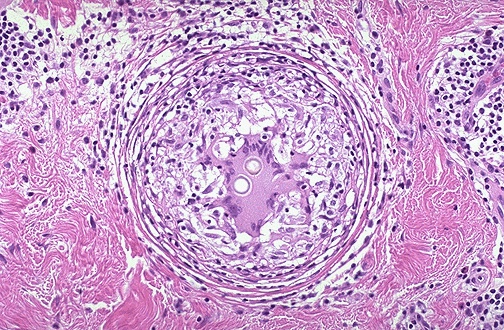

Granulomatous inflammation occurs in response to some agents which persist for a long time and require a more orchestrated immune response to fight them. The granuloma seen here demonstrates the typical rounded and focal nature of this type of inflammation. A couple of spherules of C. immitis are present in the giant cell in the center. |